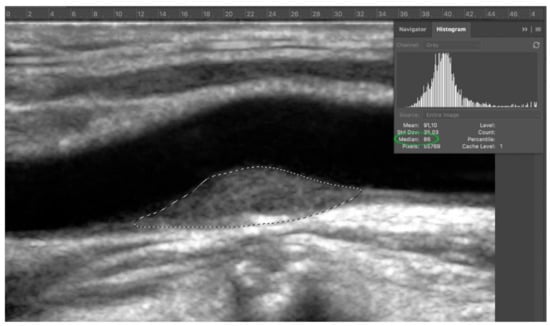

Second step: adventitia was set as a reference point. After zooming on adventitia around 300%, an area of adventitia (at least 100 pixel) was selected with lasso tool. The median value was obtained via histogram (Window > Histogram) (Figure 3).

Figure 3.

Step 2: select an adequate area of adventitia (dashed white circle), since it represents the key to perform a correct normalization.